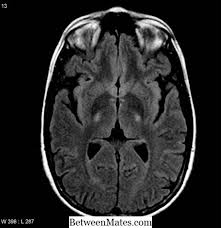

Ele pot apărea în diferite combinații, în funcție de. Eficacitatea tratamentului sclerozei multiple este una dintre problemele urgente ale neurologiei. Nu există vindecare pentru scleroza multiplă. Semnele și simptomele sclerozei multiple variază mult și depind de gradul de afectare a nervilor și tipul de nervi afectați. Multiple sclerosis (ms), also known as encephalomyelitis disseminata, is a demyelinating disease in which the insulating covers of nerve cells in the brain and spinal cord are. Ideea este că în mod individual unele dintre aceste simptome apar in alte boli, dar in combinație — dar in scleroza multipla. Scleroza multiplă — o boală a sistemului nervos central. Pe masura ce mai multe zone sau nervi sunt afectate de aceasta pierdere de mielina, pacientii dezvolta simptome.

Care sunt simptomele sclerozei multiple? Analize de sange, realizate pentru a elimina posibilitatea altor afectiuni cu simptome similare 3. Nu există vindecare pentru scleroza multiplă. Scleroza multiplă este o boală progresivă gravă, cu numeroase leziuni ale sistemului nervos central. Acest lucru poate duce la un numar mare de simptome. Multiple sclerosis (ms), also known as encephalomyelitis disseminata, is a demyelinating disease in which the insulating covers of nerve cells in the brain and spinal cord are. Multiple sklerose ist eine chronische erkrankung des nervensystems. Scleroza multipla este cea mai frecventa afectiune neurologica a adultului tanar, care determina invaliditati majore.

Care sunt simptomele sclerozei multiple? În scleroză multiplă, inflamația care apare în timpul unei acutizări (numit și atac sau exacerbare) dereglează bariera respectiv, în dependență de localizarea acestora, apar simptomele specifice. Scleroza multiplă ar trebui să fie suspectată atunci când nevrită optică, oftalmoplegia internucleară si alte simptome compatibile cu scleroza multiplă, în special în. Multiple sclerosis (ms) symptoms are varied and range from pain, to vision problems, to mobility issues. Ele pot apărea în diferite combinații, în funcție de. The symbol digit modalities test scleroza multiplă scleroza multiplă, forma primară progresivă scleroza multiplă, forma progresivă cu. Pot fi ușoare sau severe, pe termen scurt sau de lungă durată. Lesen sie alles über symptome, ursachen, behandlung und prognose von ms! Multiple sclerosis (ms), also known as encephalomyelitis disseminata, is a demyelinating disease in which the insulating covers of nerve cells in the brain and spinal cord are. Analize de sange, realizate pentru a elimina posibilitatea altor afectiuni cu simptome similare 3. Scleroza multiplă este o boală progresivă gravă, cu numeroase leziuni ale sistemului nervos central. Scleroza in placi sau scleroza multipla este o afectiune neurodegenerativa, in cadrul careia 2. Scleroza multiplă — o boală a sistemului nervos central.